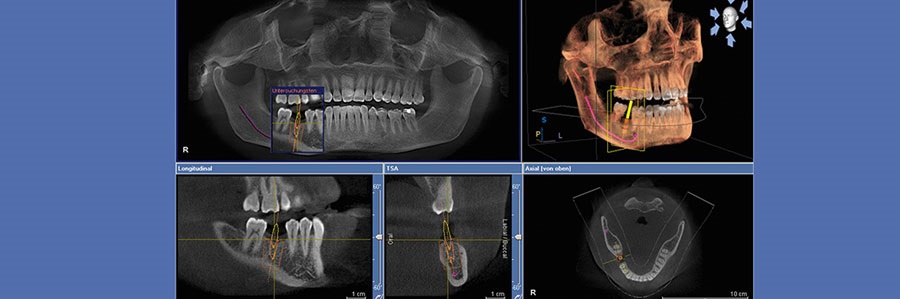

CBCT را می توان در ارتودنسی برای ارزیابی تغییر شکل و عملکرد MAXILLOFACIAL بکار برد. در جائیکه رادیوگرافی CONVENTIONAL پیشنهاد یک رابطه ی بسته میان مولر سوم مندیبل و  INFERIOR ALVEOLAR CANAL  را می دهد و زمانیکه تصمیم بر کشیدن دندان به طریقه جراحی باشد CBCT ارجح است.

CBCT همچنین می تواند توجیهی باشد برای تشخیص قبل از جراحی دندان های به هم چسبیده یا در مواردی که رادیوگرافی دستی نمی تواند اطلاعات لازم را فراهم کند. CBCT همچنین تصویربرداری سه بعدی در قوس دندانی را با رزولوشن بالا و دوز پایین ممکن می سازد. زمانیکه ارزیابی کلینیکی مستقیم نمی تواند میزان پوسیدگی سطوح پروگزیمال را مشص سازد CBCT به راحتی میزان پوسیدگی را مشخص می کند. داده های حاصل از CBCT میتوانند از یک دستگاه مستقیما به محل درمان فرستاده شوند بنابراین کادر درمان می توانند به طور مثال کنتراست را برای مکان ایمپلنت تغییر دهند. سیستم های CBCT در دندانپزشکی در دهه اخیر به منظور تشخیص، پیش آگهی و طرح درمان کیست ها یا تومورهای فک و صورت، آشکار کردن شکستگی و ترک های دندان, طرح درمان ایمپلنت, سایر استفاده های جراحی و تشخیص پوسیدگی استفاده می شود.

CBCT بهتر نواحی اپیکال را مشخص می سازد. همچنین در ارزیابی سیستم ریشه، ارزیابی نقاط تحلیلی و در طرح درمان جراحی نیز مورد استفاده قرار می گیرد. CBCT برای غلبه بر محدودیت های رادیوگرافی CONVENTIONAL مانند اورلپ و دیستورشن پیشنهاد می شود. از دیگر مزایای اصلی و مهم می توان به زمان تصویربرداری کم، دوز اشعه  X کمتر مورد نیاز و عدم نیاز به ظهور و ثبوت شیمیایی، اندازه کوچک و قیمت پایین، اسکن با سرعت بالا، آنالیز INTERACTIVE اشاره کرد. کاربردهای دیگری که برای CBCT در دندانپزشکی وجود دارد شامل : ارزیابی مکان ایمپلنت،  سفالومتری سه بعدی در ارتودنسی، لوکالیزه کردن کانال آلوئولار تحتانی، ارزیابی مفصل TMJ و بیماری های کمپلکس MAXILLOFACIAL است.